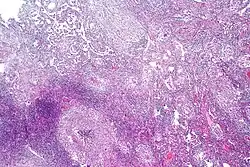

Pulmonary tuberculosis characterized by granulomatous inflammation with necrotizing epithelioid granulomas. Low power view. H&E stain. -